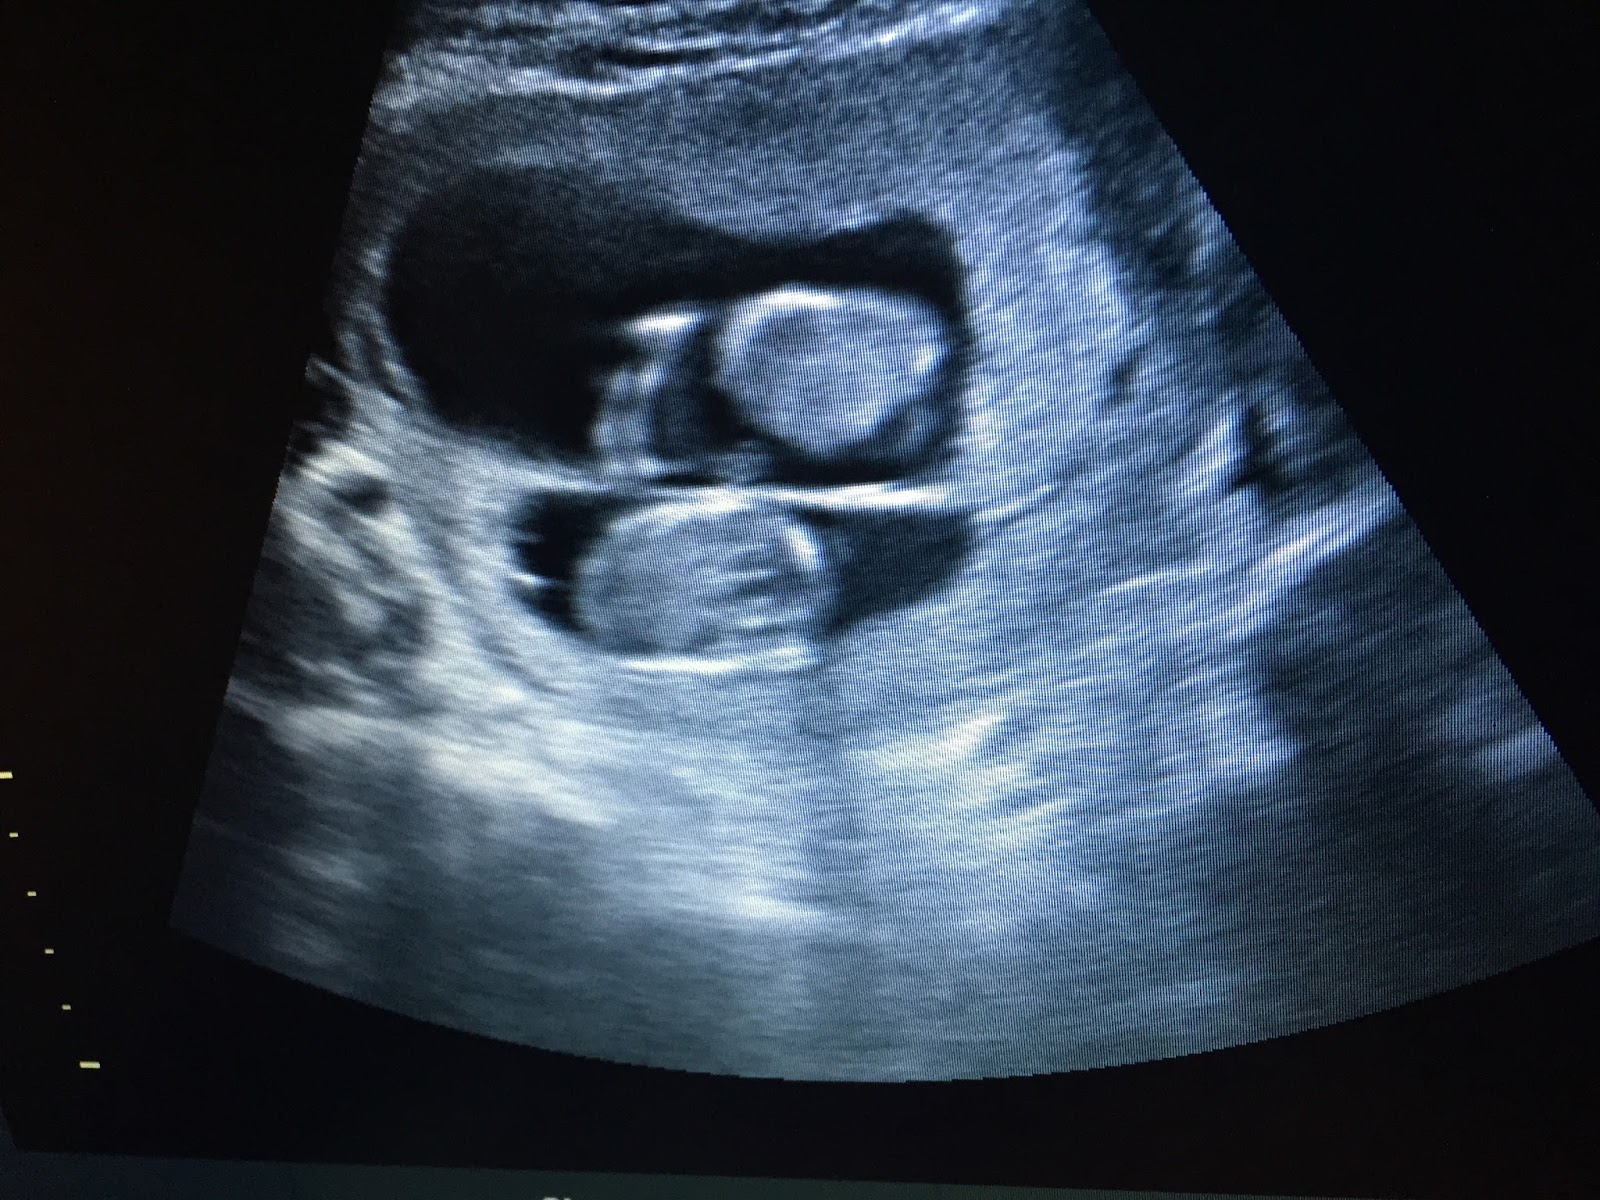

At my OB appt, just after 18 weeks, we were able to do a gender ultrasound. We were SO excited. I have been dying to know what the babies are. To tell the boys we filled balloons with confetti and had each of them pop one. They were shocked (as were we) but so excited to find out we are having TWO BOYS!!! I couldn't be happier! I love having boys and I feel so lucky in so many ways.

Hello babies!!! These pictures are from our gender ultrasound. Baby A (below) has a profile that is the spittin' image of Will! Can't wait to see the boys when they are born and see who they look like. I thought for sure we were having a boy/girl. So I was surprised when it was two boys. But honestly, I couldn't be happier. Every once in awhile I think "Oh, I'll never know what it's like to raise a girl" but I haven't been sad about it. There are so many things I love about having boys, I think it will be so much fun. Plus I love that the boys will all have a fun and unique relationship with Scott, and with each other. I love that I get to raise FOUR missionaries, and four little men to become husbands and providers. I couldn't be happier.